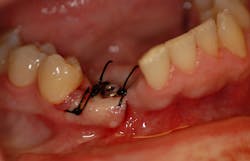

A 37-year-old male presents with a history of trauma to the anterior mandible. At the time of the incident, teeth Nos. 26 and 27 were extracted without ridge preservation. The patient was left with large crestal and buccal defects postextraction (figures 1 and 2).

A full-thickness flap is reflected to visualize the bone and confirm positioning through the surgical guide. The guide is designed with windows to visualize proper seating. The surgical guide fully limits the implant drill in all dimensions, including depth, making it possible to drill to the final osteotomy depth and width with one drill. The implant fixture was placed and allowed to heal for four months with a healing abutment. The presurgically planned prosthesis was lab fabricated and delivered (figures 6 and 7).